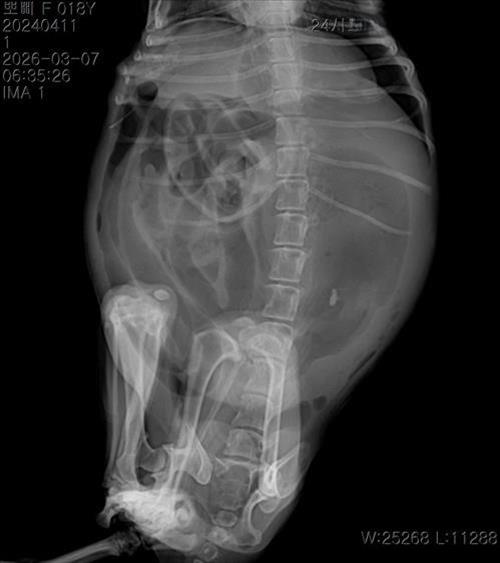

17살 말티즈 1.6 kg 였습니다. 엑스레이 하나는 복부팽창 찍은 이떄 혼수상태 일겁니다 또 다른 하나 사진은 이미 혼수상태 쇼크상태에서 천자 한 후 찍은 엑스레이 사진입니다

의사말 1번쨰 엑스레이 찍었을때 장기파열 두번쨰 뽀삐가 쇼크가 오고 혼수상태 일때 천자후 두번쨰 엑스레이 찍을때는 큰 덩어리로 보이는 종양 이라고 하였습니다